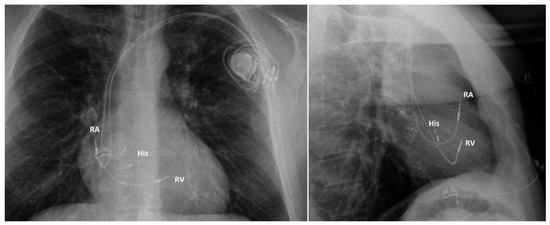

Direct His bundle pacing has recently attracted interest as a more physiological alternative to right ventricular or biventricular stimulation. The advent of new tools has facilitated the implantation procedure. This report relates our initial experi...